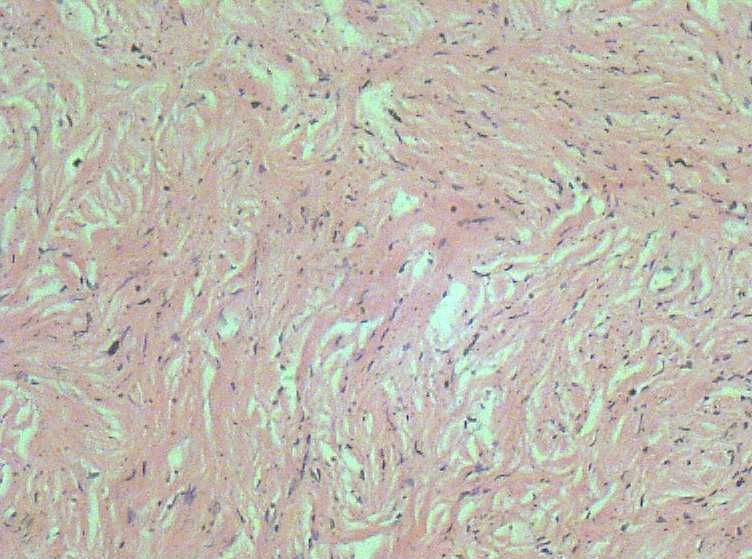

29 左侧卵巢肿瘤大小8*6*6质硬、输卵管外观正常。右附件外观正常

肉眼检查:(腹腔镜术)苍白色圆柱状物一堆约10*10*4CM质硬,未见囊肿及出血和坏死。取一

B超医生考虑:勃伦纳瘤 ?

本人考虑纤维瘤 ,请各位老师点评下。

良性梭形细胞肿瘤,待做特殊染色定纤维瘤或卵泡膜细胞瘤。

就这几张图而言,支持纤维瘤。你再找找看胞浆里面有没有脂质空泡,与卵泡膜细胞瘤鉴别。